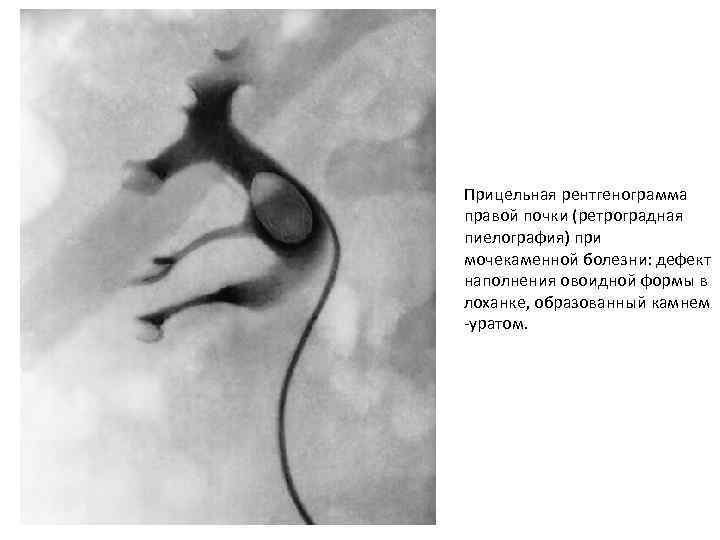

Прицельная рентгенограмма правой почки (ретроградная пиелография) при мочекаменной болезни: дефект наполнения овоидной формы в лоханке, образованный камнем -уратом.